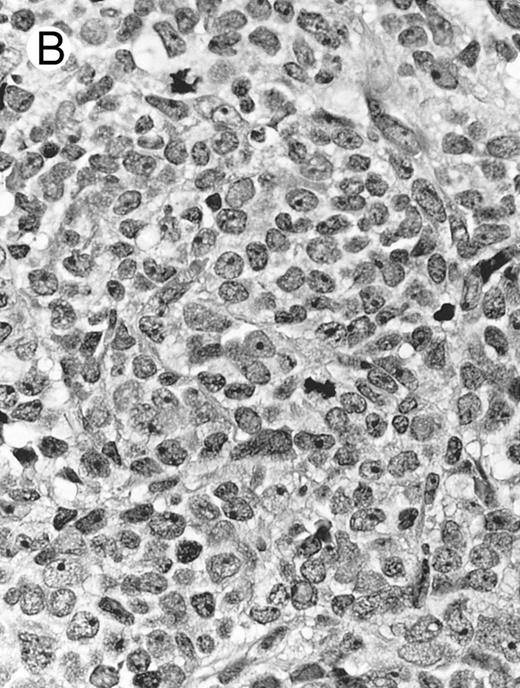

Histologically, the lymphomatous infiltrate was diffuse or patchy, with angiocentric and angiodestructive growth being observed in 30 cases (88.2%) (Figs 1 and 2). The cytologic composition was variable from case to case, including predominance of small cells, medium-sized cells, or large cells, or a mixture of these cell types (Fig 2 and 3). The tumor cell nuclei frequently showed irregular foldings and granular chromatin (Fig 2B). The larger cells possessed distinct nucleoli. The cytoplasm was moderate in amount and often pale. Karyorrhexis was usually prominent. Zonal tumor cell death, focal or confluent, was evident in 27 cases. In the 14 cases for which Giemsa-stained touch preparations were available, azurophilic granules could be identified in at least some of the neoplastic cells.

Blastoid NK cell lymphoma (case no. 40). (A) Biopsy shows a diffuse lymphomatous infiltrate with a prominent single-file pattern. (B) The neoplastic cells are medium-sized and possess fine chromatin. Mitotic figures are seen. There is remarkable resemblance to myeloid leukemic infiltration.

Blastoid NK cell lymphoma (n = 2).One patient presented with systemic disease, whereas 1 had localized disease at presentation. Histologically, the infiltrate was diffuse, with a prominent single-file pattern reminiscent of leukemia (Fig 8A). The neoplastic cells were medium-sized and had irregularly folded delicate nuclear membranes, fine chromatin, and tiny nucleoli (Fig 8B). Mitotic figures were easily identified.